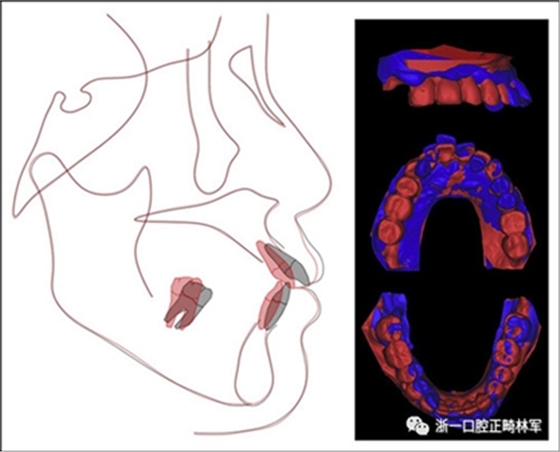

完成診斷性設計后,治療后穩(wěn)定的咬合是確定的(圖5)。進行治療之前,治療計劃和順序需要通過涉及正畸,牙周病和修復的多學科綜合治療方法加以確認(圖6)。牙周治療應在正畸治療前完成。牙周疾病的治療采用全口潔治,上頜和下頜前牙區(qū)的刮治術,以及下頜左側后牙區(qū)的翻瓣手術。休息3個月后,幾乎每個部位都實現(xiàn)了牙周袋深度縮小,探針出血幾乎沒有(表III)??刂蒲装Y后,開始正畸治療。在正畸治療期間定期進行牙周維護的復診檢查。

圖5. 治療計劃的診斷性設置

治療后頭影測量分析顯示上頜切牙的傾斜和唇部相對于E線的位置都得到改善(表II)。治療前后頭影測量圖的疊加顯示上頜和下頜切牙的向后移動伴隨著上頜切牙的推入。垂直維度在跨學科正畸綜合治療后被保持。三維模型的疊加顯示了上頜牙列的遠中移動,下頜前牙的回縮和上頜右側尖牙的推入(圖14)。

圖14.頭影測量和3維模型的疊加